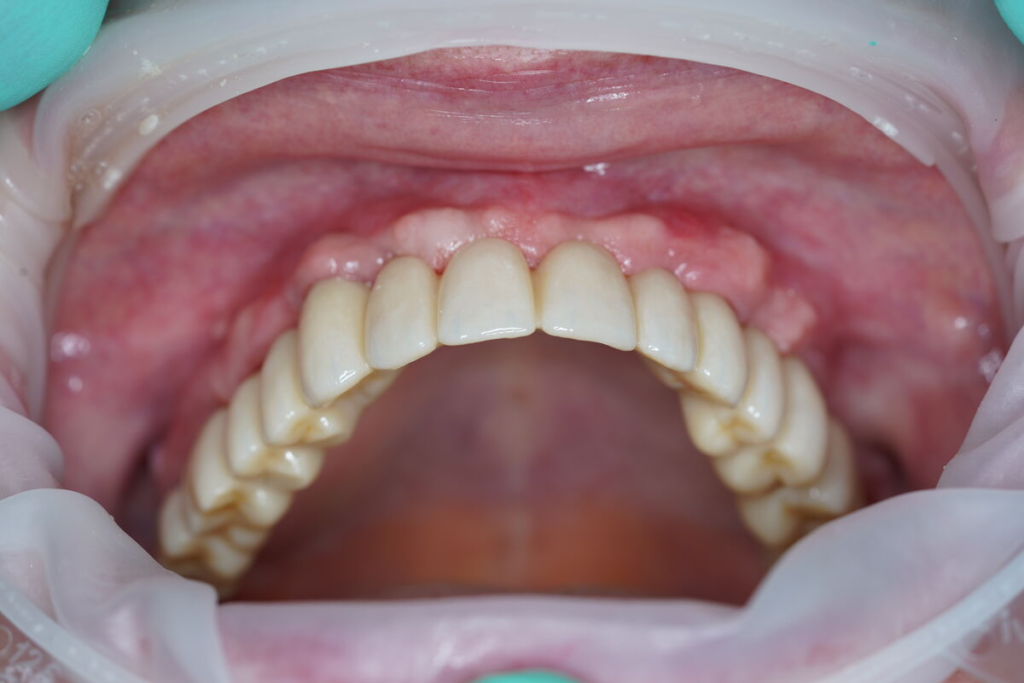

4. Finální estetická práce

Po 4–6 měsících nasazujeme trvalý můstek.

Používáme multivrstvý zirkon pro maximální estetiku, pevnost a dlouhou životnost.

Technika All-on-X — II. fáze